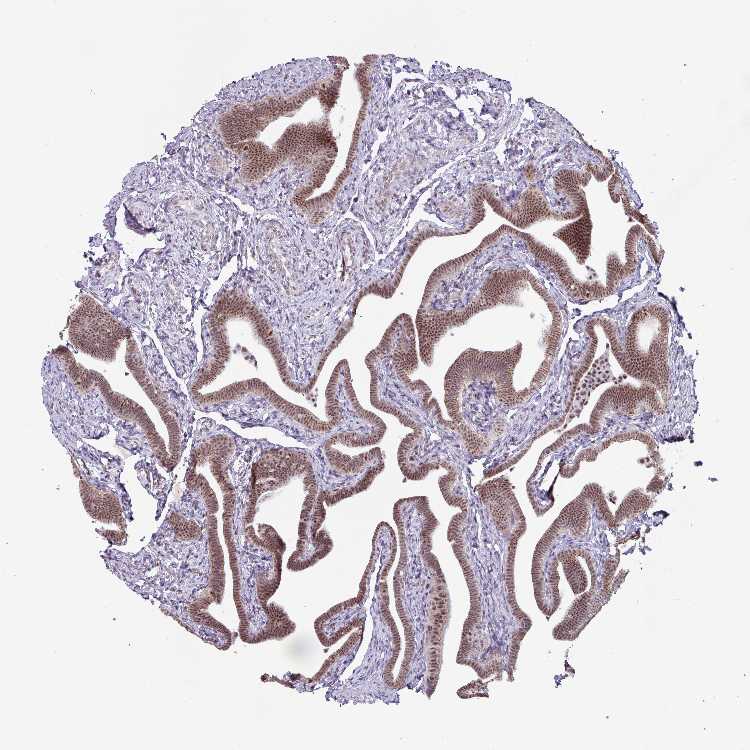

FALLOPIAN TUBE - Antibody stainingi

Antibody staining in the annotated cell types in the current human tissue is reported as not detected, low, medium, or high, based on conventional immunohistochemistry profiling in selected tissues. This score is based on the combination of the staining intensity and fraction of stained cells.

Each image is clickable and will lead to virtual microscopy that enables deeper exploration of all samples and also displays staining intensity scores, fraction scores and subcellular localization as well as patient and tissue information for each sample.

Antibody HPA052096Antibody HPA059714

Ciliated cells (cell body) Medium-

Ciliated cells (cilia axoneme) Not detected-

Ciliated cells (ciliary rootlets) Not detected-

Ciliated cells (tip of cilia) Not detected-

Glandular cells -Medium

Non-ciliated cells Medium-